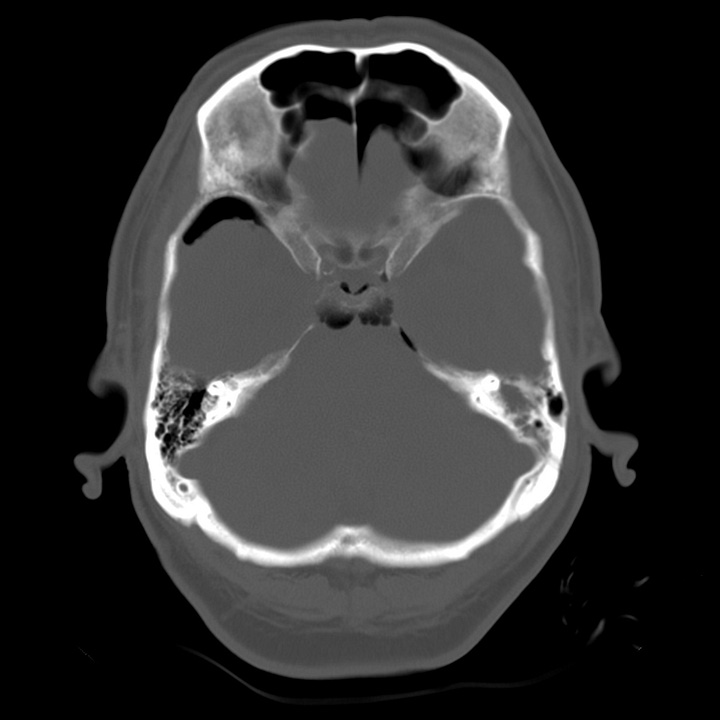

Tension pneumocephalus due to temporal bone fracture. Bifrontal subdural air collections with mild compression of the frontal parenchyma. Opacified left mastoid air cells are consistent with an acute tem- poral bone fracture. Air in the cisterns and left sylvian fissure indicate arachnoid injury.

Intracranial air is always seen after craniotomy and also occurs in a small percentage of head trauma patients, usually when a skull base or calvarial fracture traverses one of the facial sinuses or the mastoid air cells. In this case air may be seen in the epidural, subdural, or subarachnoid space. Air within venous structures is usually due to air introduced through an intravenous catheter.